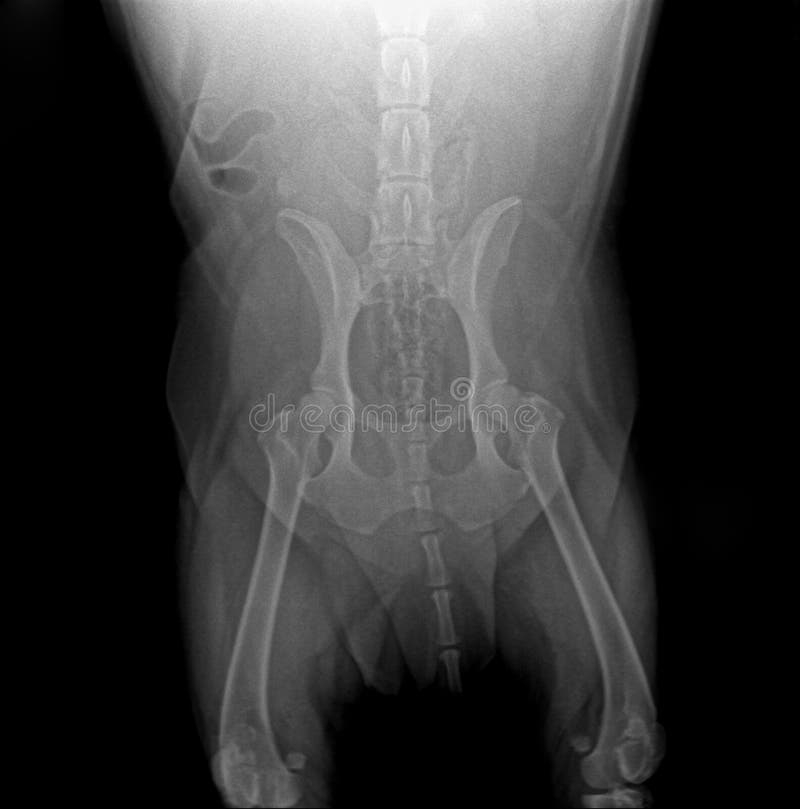

Перелом таза у собаки